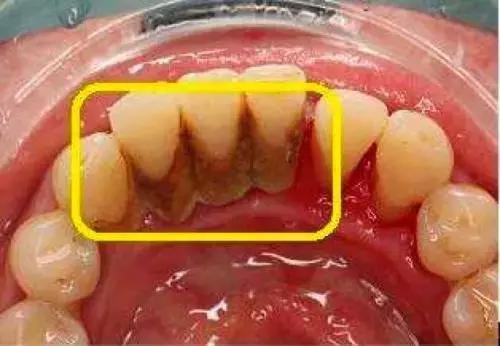

当然,不少宝宝就会有些疑问,牙结石到底是个啥玩意?什么是牙结石?牙结石又称牙石,通常存在于唾液腺开口处的牙齿表面。如下颚前牙的舌侧表面,上颚后牙的颊侧表面和牙齿的颈部,以及口腔黏膜运动不到的牙齿表面等处。

牙结石开始是乳白色的软垢,会因逐渐的钙化而变硬。它是由75%的磷酸钙,15%~25%的水、有机物、磷酸锰、矿酸钙及微量的钾、钠、铁所构成。并呈现出黄色、棕色、或者黑色。

牙结石发展过程:食物残渣→牙菌斑/牙石→(刺激牙龈)牙龈炎→(炎症导致牙槽骨吸收)牙周炎→牙齿松动→晚期牙周炎→拔除或自行脱落。想消灭牙结石?想减少牙结石的话,就要好好刷牙,最好用牙线漱口水等,从根源上减少牙菌斑的形成。

其次,就算你抠下来了还是建议你去洗个牙。因为牙结石一般都生在在牙齿根部或者是牙龈下面,如果你的牙结石都已经结块到可以抠下来了,想必牙结石肉眼可见很大一块了,这种很有可能牙龈下面还有牙结石,牙根部抠下来了牙龈里面的去洗个牙让医生看看牙龈情况,总比以后牙齿都松动了再去找牙医好。